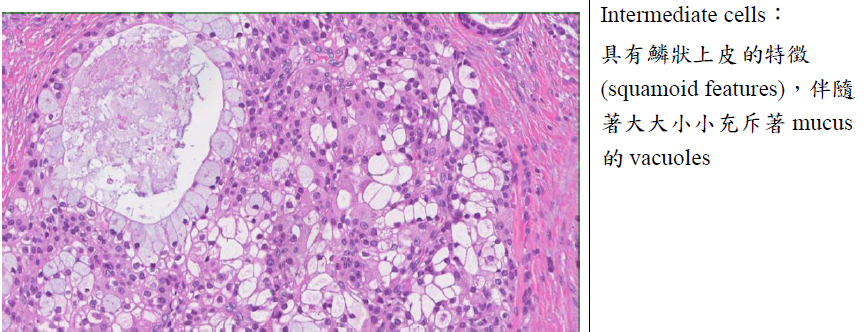

Excretory duct Mucoepidermoid carcinoma1st 2-70y

alt text alt text

• 缺乏capsule、infiltrating border

• 分成三種細胞: Squamous cell, Mucin-secreting cell, intermediate hybrids(前二之間,前驅)

alt text